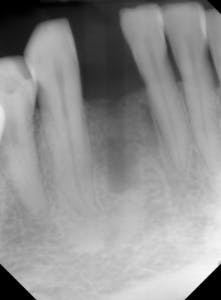

Figure 7: Following six months of healing

Figure 8: Initial implant placement DIO 3.0 x 16 mm implants